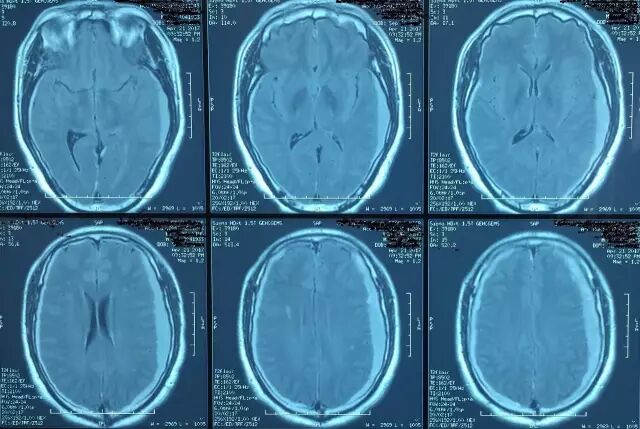

除了临床特异性的表现外,在影像学方面,SIH患者的颅脑MRI有5个典型特征(SEEPS):

(1)Subduralfluid collections硬膜下积液;

(2)Enhancement of the pachymeninges硬脑膜强化;

(3)Engorgement of venous structures静脉结构充盈 ;

(4)Pituitaryhyperemia垂体充血;

(5)Sagging of the brain脑组织下沉。其中又以硬脑膜强化及硬膜下积液最为常见。

图10. 典型病例增强MRI:硬脑膜强化合并双侧硬膜下积液。

图11. A为正常的横窦,B为扩张的横窦。

图12. A为正常脑组织矢状位,B可见脑组织下坠。